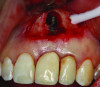

Patient 1: A 30-year-old female patient with an unremarkable medical history presented with implant No. 9 exhibiting retrograde peri-implantitis. Tooth No. 9 had been replaced with the implant 8 years prior because of a history of trauma and failed root canal treatment. The implant exhibited a periapical radiolucency with the sinus tract tracing to the apex of implant No. 9 (Figure 1 and Figure 2). The patient had a high smile line with longer clinical crowns at Nos. 9 and 10 compared with Nos. 7 and 8 (Figure 1 and Figure 2).

Fig 1 and Fig 2. Case 1: Initial clinical presentation with gutta-percha placed in the apical fistula of tooth No. 9 (Fig 1); radiograph showing gutta-percha point leading to the periapical lesion (Fig 2).

Figure 1

Figure 2